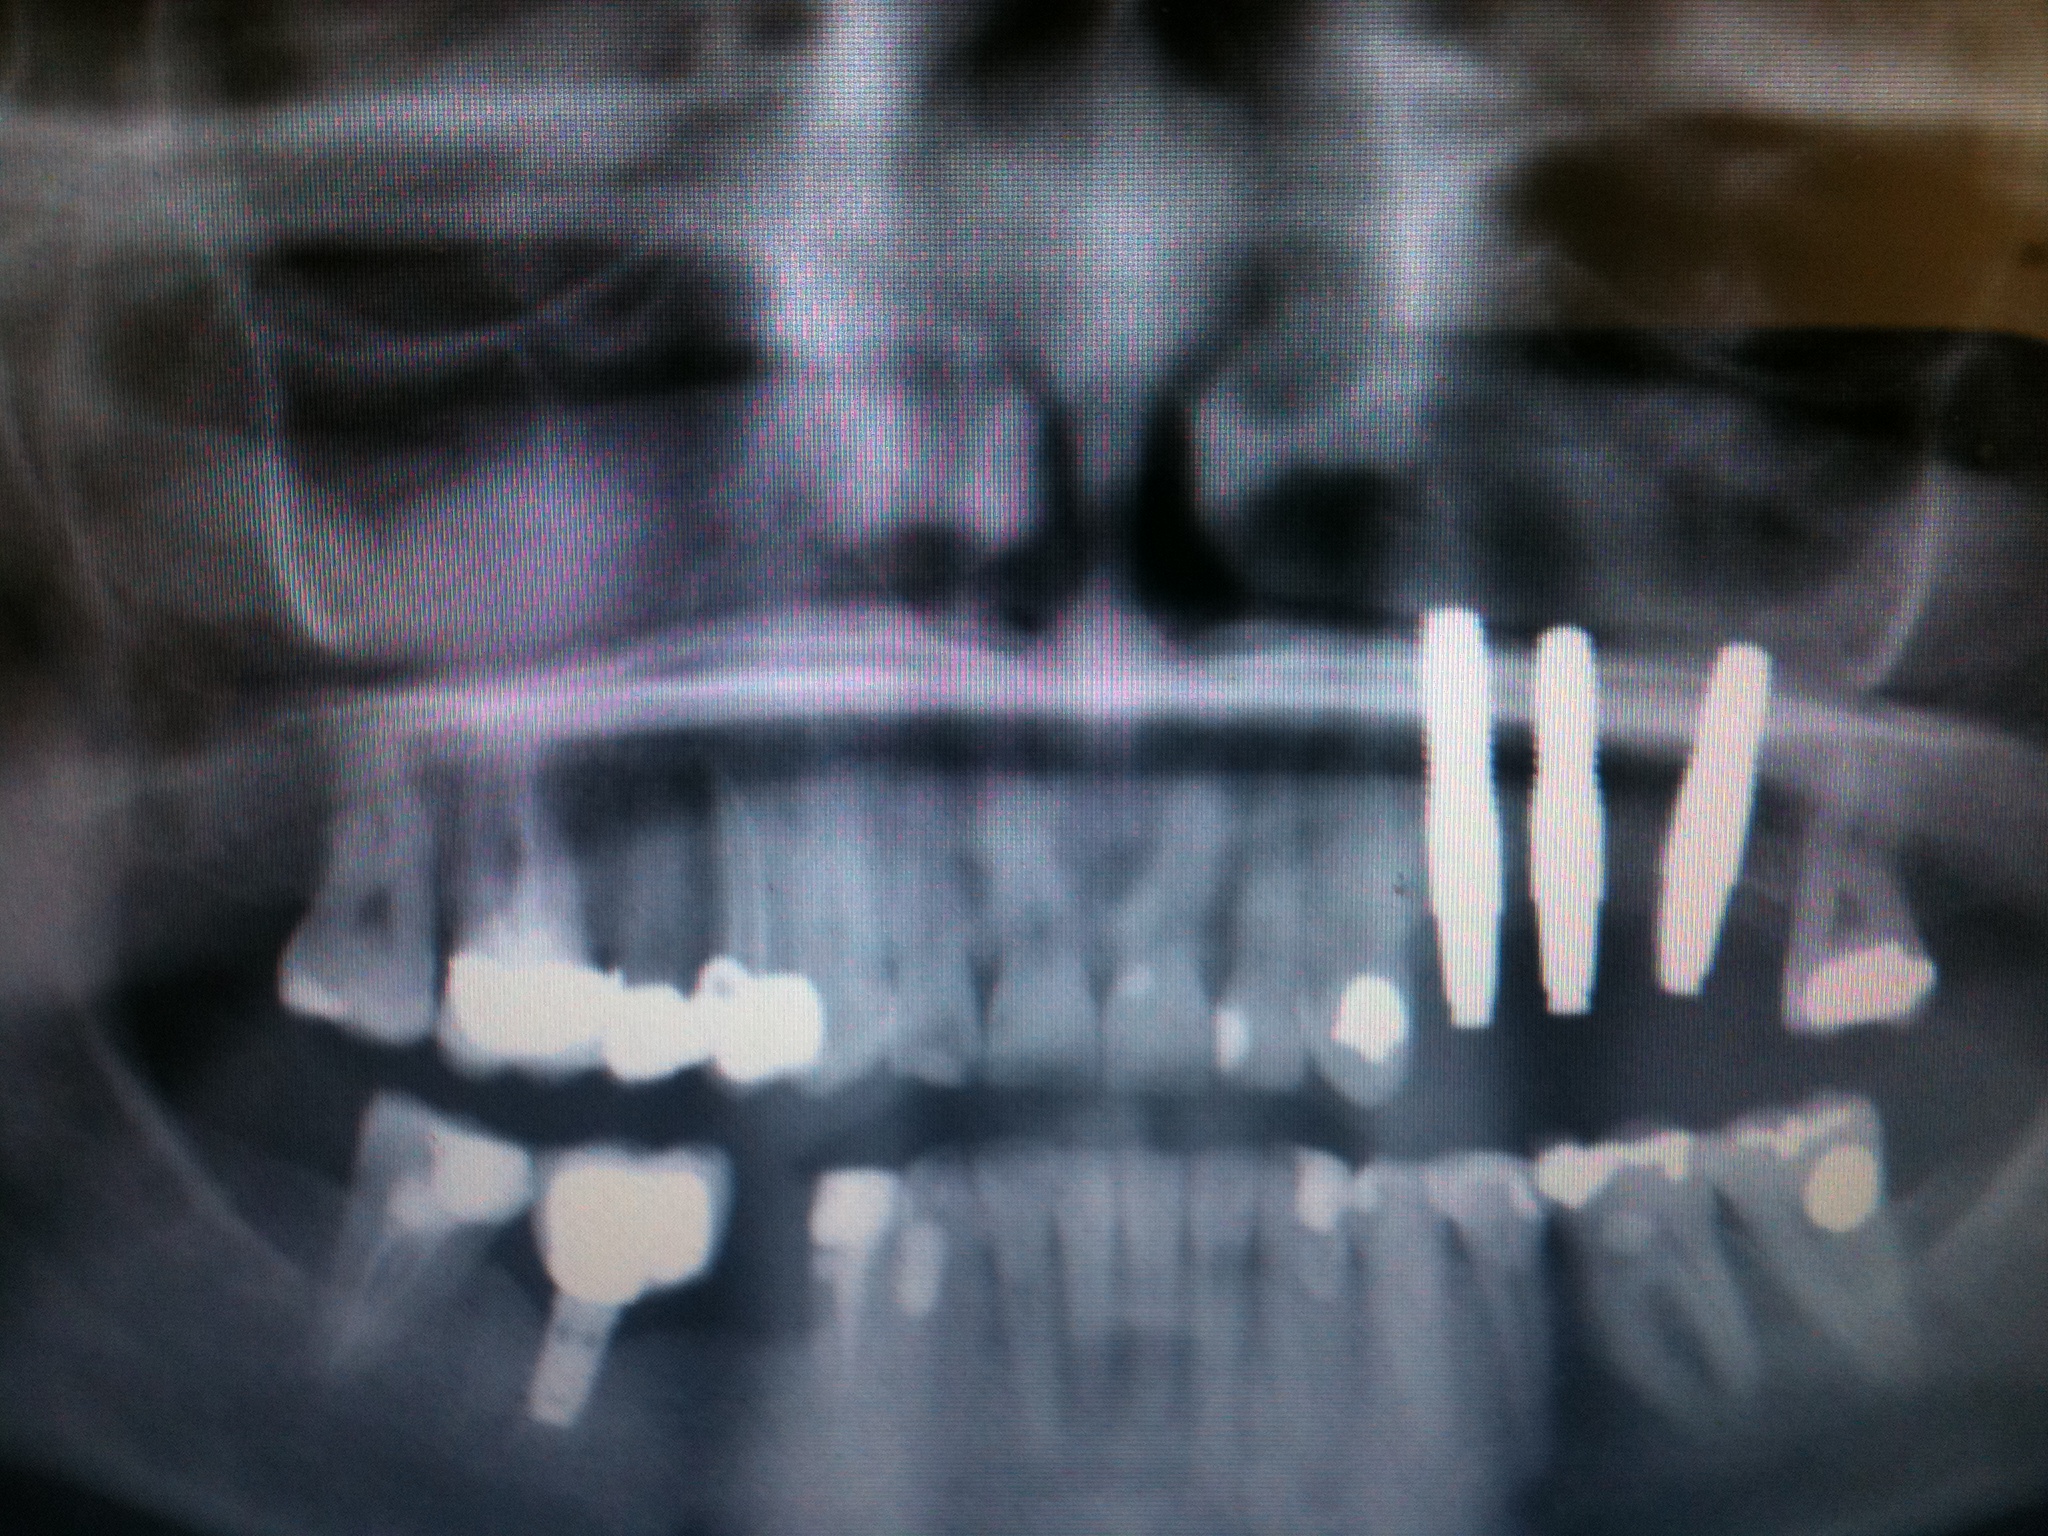

Impianto in zirconio vs impianto titanio impianto in titanio e corona-dente naturale-impianto zirconio e corona

L’impianto Ceralog Hexalobe è invece bifasico,consente l’utilizzo di soluzioni protesiche avvitabili e di conseguenza reversibili,Gli abutment sono in PEEK,è un materiale molto duttile che in condizione di carico si comporta in maniera ottimale.E’ un materiale radiotrasparente.